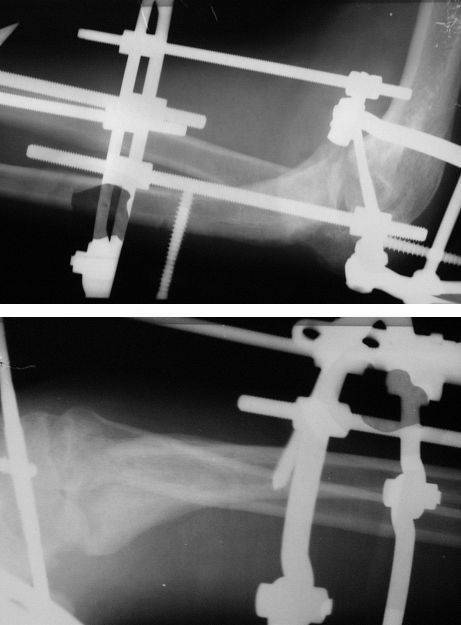

Re: Застарелый вывих предплечья с несросшимся переломом локтевого отростка

Коллеги! Сделан первый этап операции - синтез спице-стержневым аппаратом. При умеренной дистракции локтевого сустава (0,5 мм в сутки) производится дорзальная тракция дистального отломка локтевой кости (1 мм в сутки) стержнем Штеймана при стабилизации olecranon отдельным стержнем. Стержень в olecranon ввелся очень легко - остеопороз. Р-граммы через 4 дня после операции.